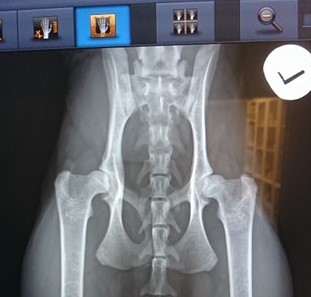

Dagen etter sin 1-års dag var Indrusen inne til røntgen for å sjekke sine hofter i forbindelse med avl. Jeg hadde ikke så store forhåpninger da jeg fikk se på bildene, og regnet derfor med at det ville nok være i hvert fall mild dysplasi…

(Hun tok også bilder av ryggen for å være sikker på at det ikke skjulte seg noe grums der ettersom hennes linjer ikke er gjennomtesta. Null spondylose!)

I dag har vi fått svaret på avlesinga av bildene av Indras hofter fra PawPeds, og jeg fikk rett i mine antakelser. Jeg var dog overlykkelig over at det ikke ble verre enn det ble!